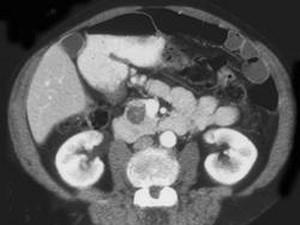

患者,女,57岁,上腹部隐痛半年余,CT片,最可能的诊断是 ( )A、胰腺囊腺瘤B、胰岛细胞瘤C、胰腺脓肿D、胰腺假性囊肿E、胰腺癌

问题 患者,女,57岁,上腹部隐痛半年余,CT片,最可能的诊断是 ( )

选项 A、胰腺囊腺瘤 B、胰岛细胞瘤 C、胰腺脓肿 D、胰腺假性囊肿 E、胰腺癌

答案 A